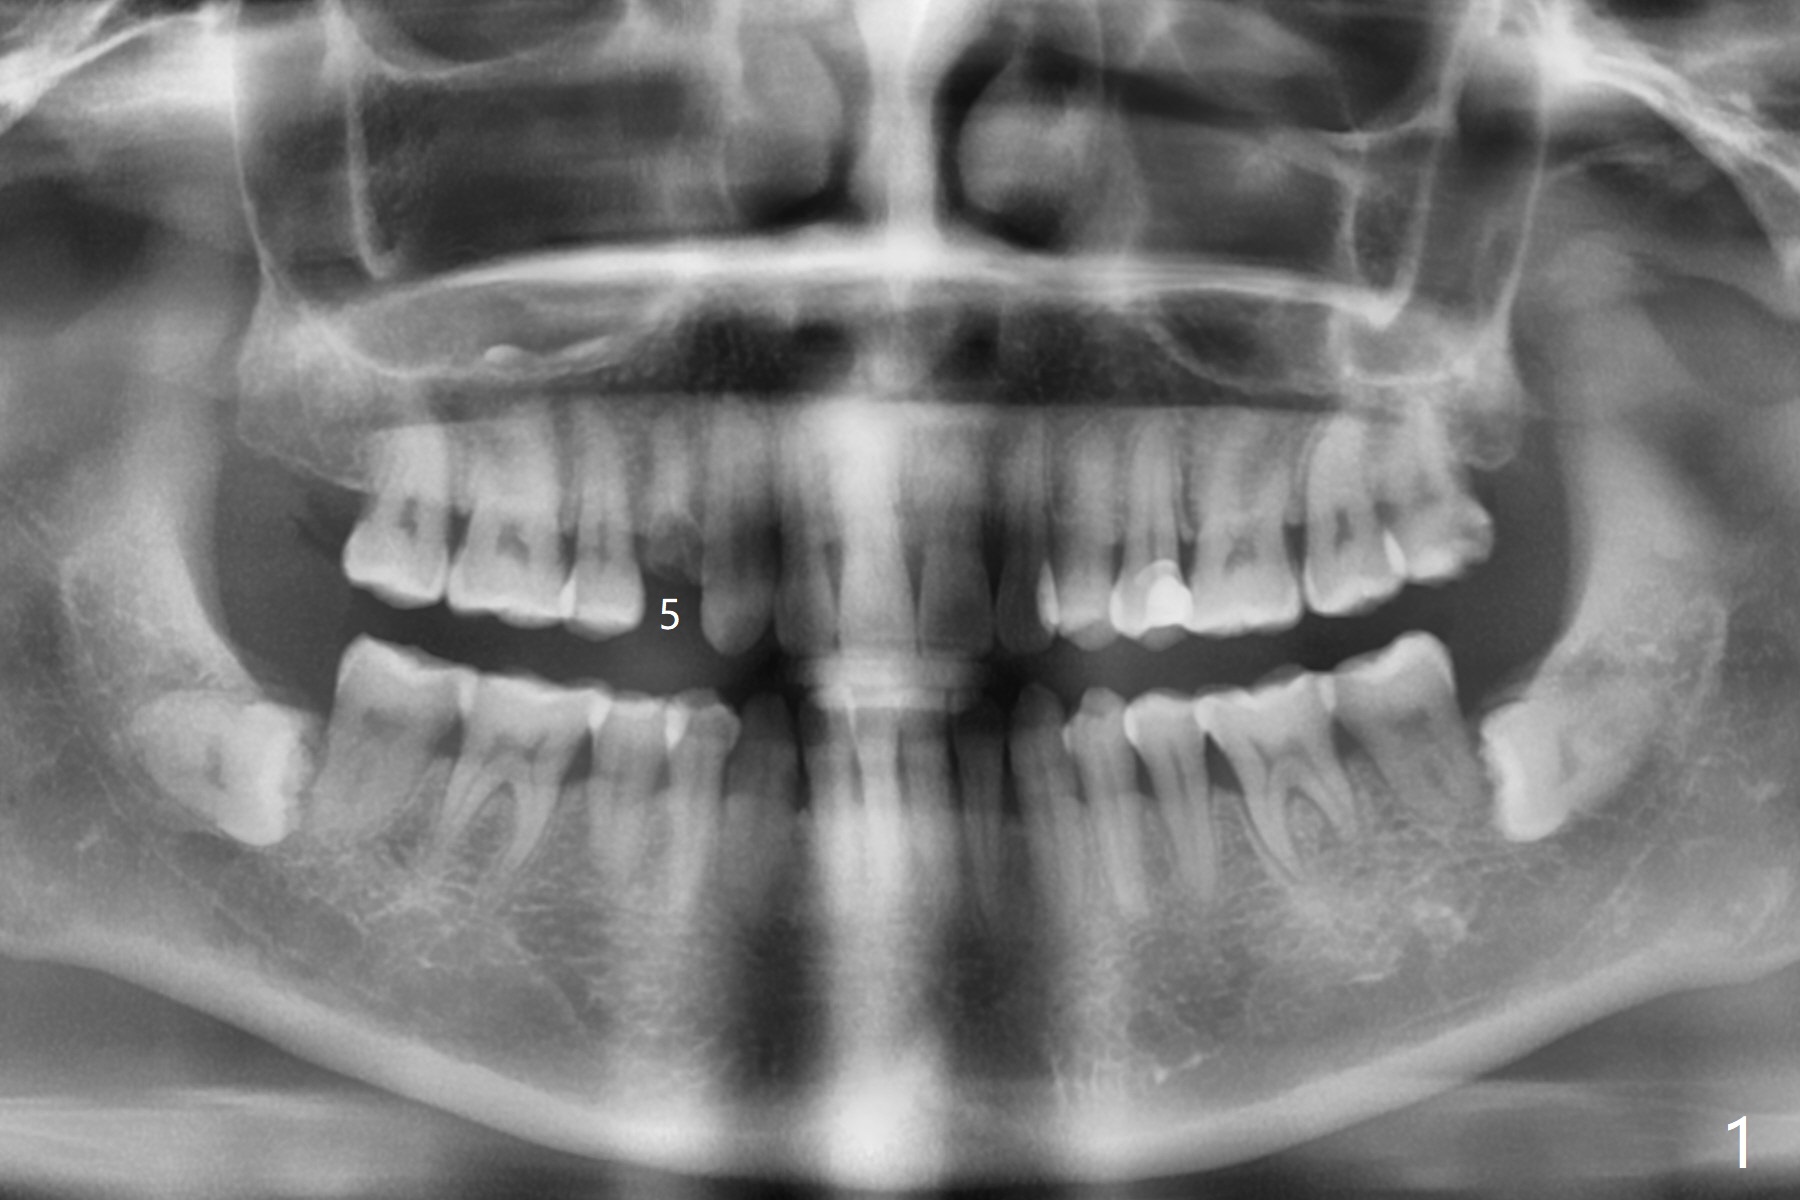

A 46-year-old woman requests implant after equigingival fracture at #5 (Fig.1). The long bone without bone loss makes it easy for immediate implant (Fig.2). PRF is not required.